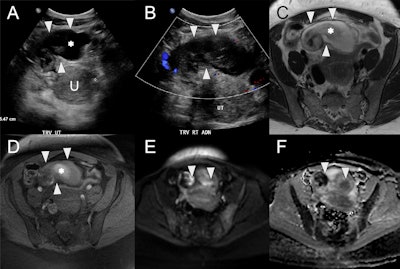

Right pyosalpinx in a 42-year-old female with infectious symptoms and vaginal discharge postspontaneous abortion. (A) Axial ultrasound showing a distended tubular cystic structure (white arrowheads) anterior and to the right of the uterus (U, calipers) with internal echogenic debris (asterisk). (B) Ultrasound demonstrates no color Doppler flow within this structure (white arrowheads). (C) Axial T2w MRI of the uterus with a high signal intensity tubular structure (arrowheads) within the anterior pelvis, corresponding to the right uterine tube and containing intermediate to low signal debris (asterisk). (D) Axial fat-suppressed T1w MRI of the uterus shows high signal debris (asterisk) within the right uterine tube (white arrowheads). Axial high b-value diffusion-weighted image (E) and apparent diffusion coefficient map (F) demonstrate diffusion restriction of internal contents (white arrowheads), which, given the clinical context, is consistent with pus.

MRI is the most sensitive modality to differentiate pyosalpinx (restriction on diffusion-weighted imaging), hematosalpinx (hyperintense on T1-WI), and hydrosalpinx (hypo- or isointense on T1-WI), they added. “CT and MRI also allow for diagnosis of additional complications such as septic thrombophlebitis and liver capsule adhesions (Fitz-Hugh-Curtis disease).”